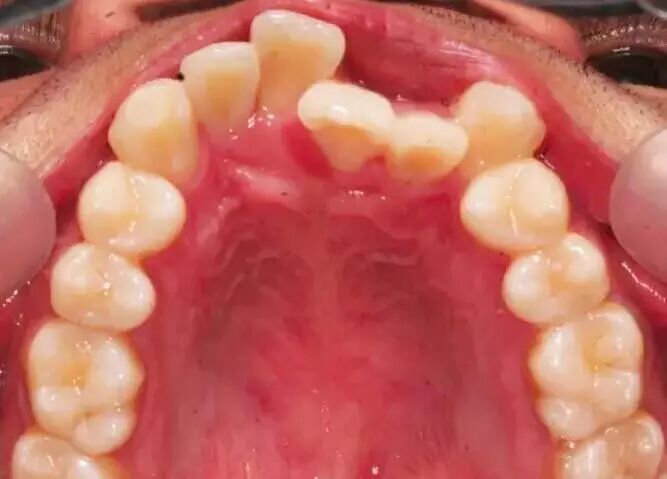

比如,这位患者朋友,在做矫正之前牙齿是这样的:

由于牙齿过于不整齐,患者拔除了四颗牙齿(上牙和下牙各拔两颗),然后通过戴牙套的方式,进行牙齿矫正,牙齿明显变的整齐: